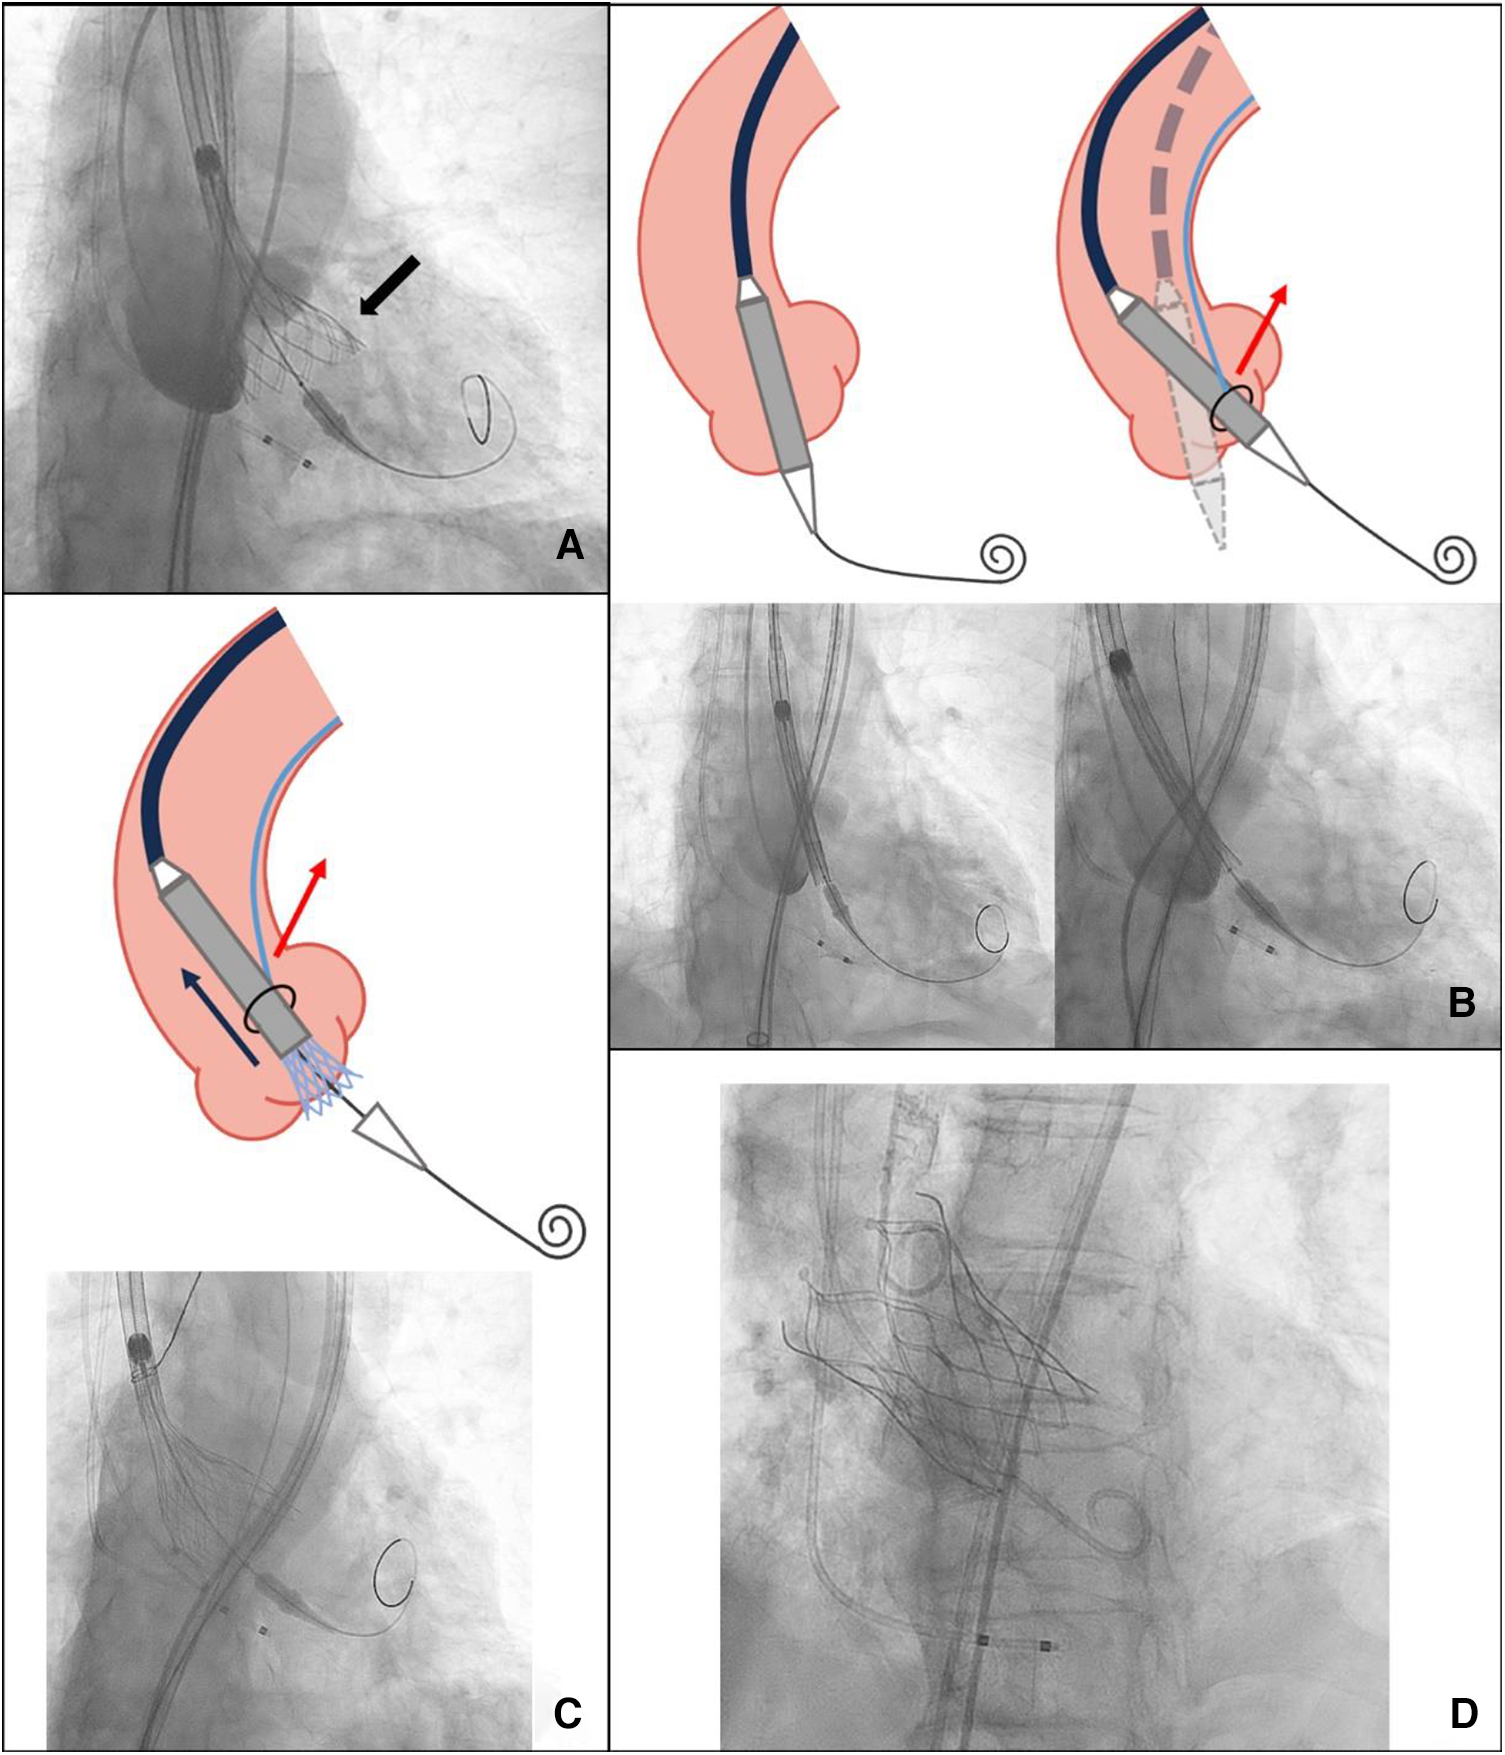

Figure 2

(A) An excessively deep implantation of the valve in the left coronary sinus (black arrow). (B) The coaxiality with and without SACOT. (C) SACOT continuously optimizing THV coaxiality during deployment. (D) Successful implantation. SACOT, snare-assisted coaxiality optimized technique during valve deployment.

Therefore, we decided to pre-place a snare. The snare system, with a loop diameter of 20 mm and a 90° angle, was employed. A 4-F sheath was advanced through the ipsilateral femoral artery, with the prosthesis captured at the level of the descending aorta. The snare captured the distal fifth of the delivery capsule. During the second deployment, we used an unconventional approach by continuously pulling the prosthesis during deployment to enhance coaxiality until it reached the stable position. This led to a more optimal implantation depth below the left coronary sinus (Figures 2B–D). After the TTE assessment, no apparent perivalvular leak was observed, and there was no impact on the anterior leaflet motion of the mitral valve. We withdrew the snare catheter and released the prosthesis completely under rapid pacing at 120 beats/min to ensure valve stability. Upon a follow-up TTE before discharge, the LVEDd had decreased to 56 mm, and no residual AR was observed. The CT scan confirmed proper positioning and normal function of the THV (Figure 3).

Previously, case reports and case series have described snare-assisted TAVR as a solution for patients with severely tortuous or calcified aortas to avoid vascular complications (5). It has also served as a bail-out technique to facilitate THV passage through the aortic valve in cases with horizontal aortas or severely stenotic aortic valves. Typically, the operator withdraws the snare catheter once the prosthesis is in the correct position. In this patient, the proximal ascending aorta width measured 44.9 mm, with an aortic angulation of 62°. Conventional self-expanding valve deployment in such cases may result in poor coaxiality and excessive implantation depth, potentially resulting in paravalvular leaks or valve migration. We attempted a novel technique, which we named the “snare-assisted coaxiality optimized technique” (SACOT) during valve deployment. After the prosthesis was sent to the correction position, the snare catheter was not withdrawn. In cases where continuous adjustment of coaxiality is necessary during valve deployment, the snare can capture the prosthesis in the distal fifth and maintain the necessary tension to optimize the coaxiality during the deployment process until the valve is released into a stable position.